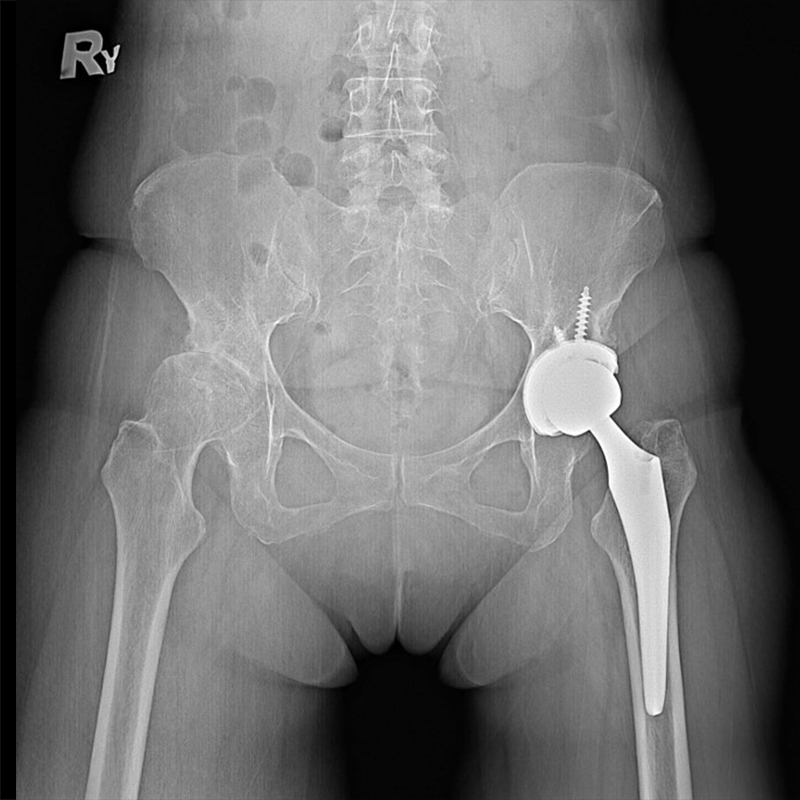

機器手臂手術 首頁 案例分享 髖關節手術 機器手臂手術 72歲 楊女士 退化性關節炎 術前 術後 60歲 彭先生骨股頭壞死 術前 術後 53歲 王女士退化性關節炎(DDH先天發育不全 CROWE TYPE 2) 術前 術後 83歲林女士退化性關節炎 術前 術後 83歲林女士退化性關節炎 術前 術後 楊女士 70歲 術前 術後 蔡女士 60歲 術前 術後